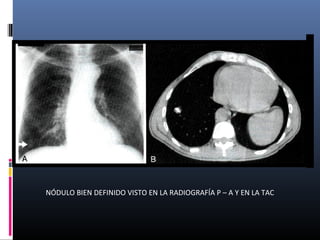

NÓDULO BIEN DEFINIDO VISTO EN LA RADIOGRAFÍA P – A Y EN LA TAC

NÓDULO BIEN DEFINIDOVISTO EN LA RADIOGRAFÍA P – A Y EN LA TAC